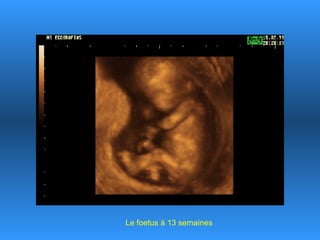

Le document traite des progrès scientifiques réalisés dans le domaine des échographies 3D. Il montre l'évolution des images du fœtus à différentes étapes gestationnelles, illustrant la clarté des images obtenues au fil du temps. Cette avancée technologique est présentée comme impressionnante, notamment pour le fœtus de 18 ans.